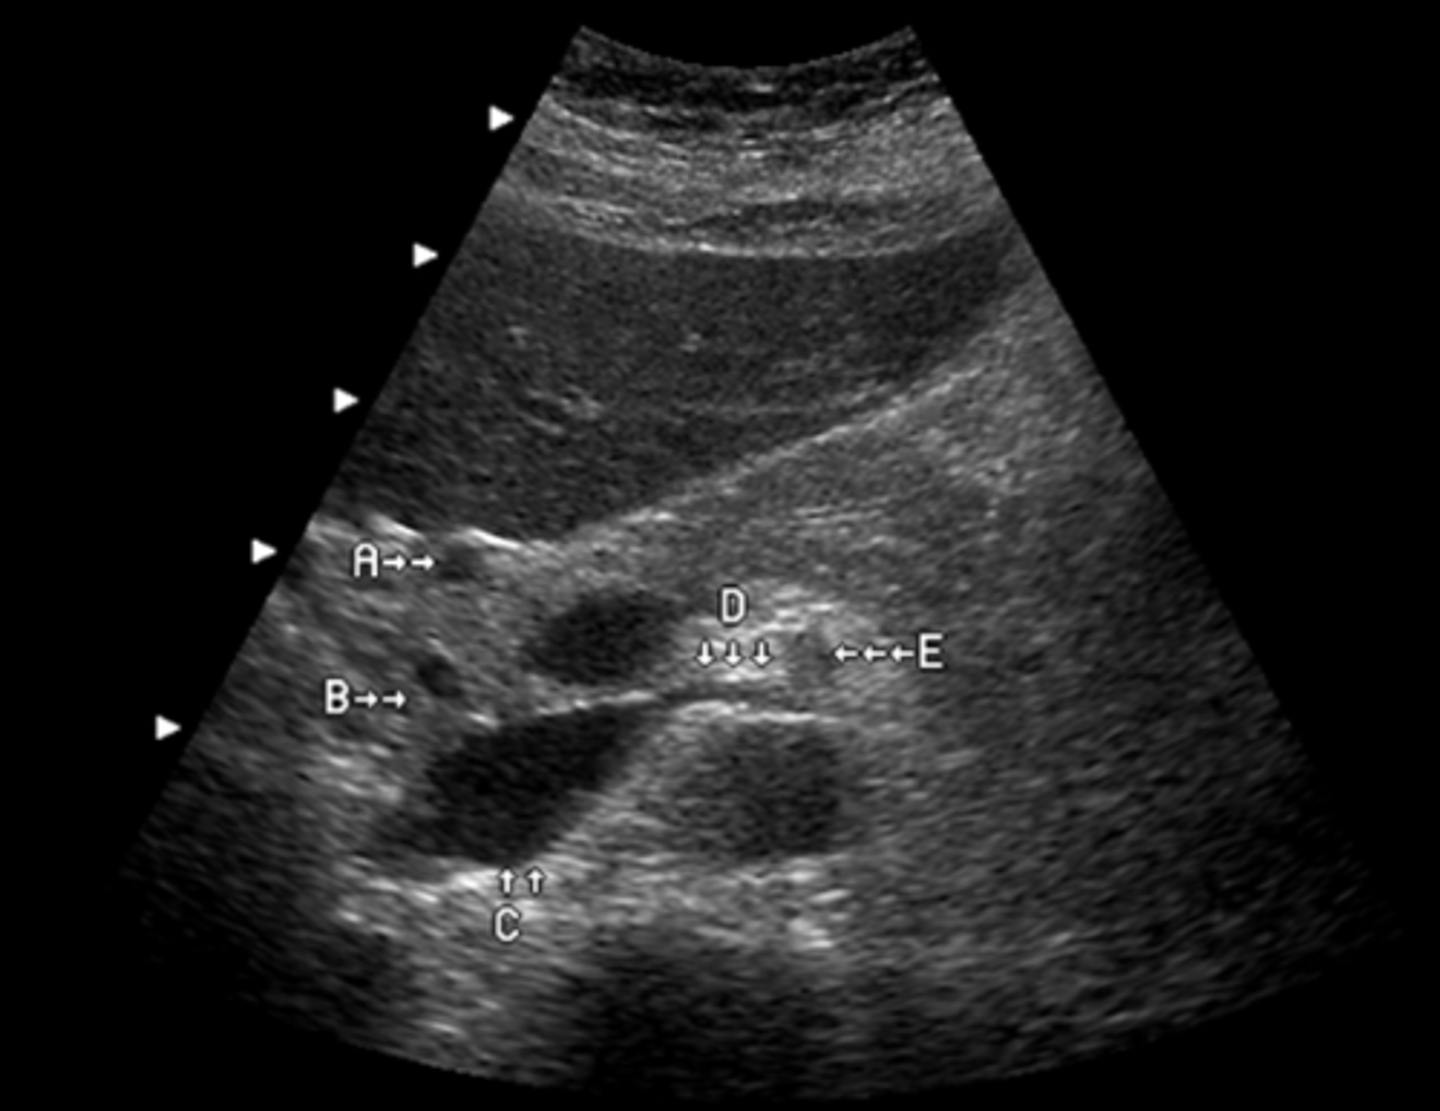

The arrow labeled D is pointing to what lobe of the liver?

a. medial segment of left lobe

b. lateral segment left lobe

c. posterior segment right lobe

d. anterior segment right lobe

e. caudate lobe

b. aorta

What vessel is seen posterior to the vessel labeled D?

a. IVC

c. right renal artery

d. IMV

e. splenic vein

a. left lobe

What lobe of the liver does the letter A represent?

b. caudate lobe

c. posterior right lobe

d. anterior right lobe

e. quadrate lobe